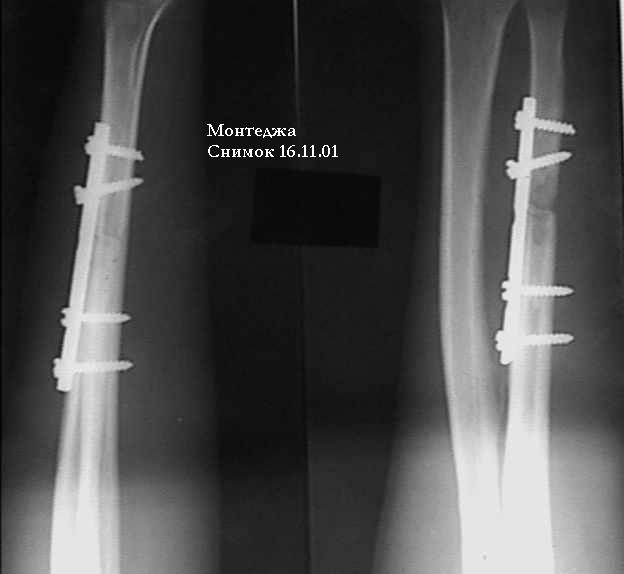

У больного травма в октябре 2001. Перелом Монтеджа разгибательный.Проведена операция металлостеосинтез пластиной, винтами локтевой кости. Вывих головки лучевой кости не диагностирован. В конце февраля 2002 г снята гипсовая повязка. Имеется ограничение сгибания до 115 градусов. Больной обратился в наше лечебное учреждение 07.02.02. Мы предложили ему оперативное лечение. Планируем провести резекцию головки лучевой кости. Есть мнение попытаться вправить головку лучевой кости, провести пластику кольцевидной связки, фиксисировать головку лучевой кости трансартикулярно спицей. Но боюсь, что в момент остеосинтеза была укорочена локтевая кость, поэтому необходимо будет провести резкцию в области диафиза лучевой кости, а затем провести остеосинтез лучевой кости. Рентгенограммы: